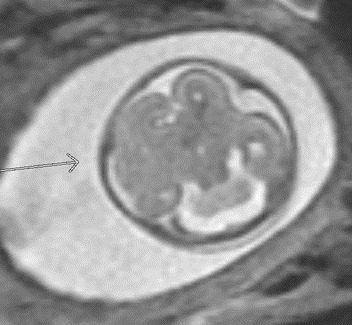

A 24-year-old gravida 1 with a dichorionic-diamniotic twin pregnancy at 16w1d gestation was evaluated by Maternal-Fetal Medicine who identified multiple possible cranio-facial abnormalities in Twin A on transabdominal ultrasound. This raised the concern for a possible chromosomal abnormality as well as holoprosencephaly as the cavum septum pellucidum was not visualized. A detailed transabdominal ultrasound performed at 16w1d provided the initial assessment of the abnormal-appearing left cerebrum of Twin A (Figure 1). The left cerebral ventricle was overall poorly visualized, however, the posterior aspect of the left ventricle appeared to be significantly more dilated compared to the normal-appearing right ventricle. The cavum septum pellucidum could not be visualized, the thalami appeared fused, and the temporal areas of the facies appeared more angulated than expected. The patient was scheduled for a fetal MRI which was performed at 19w1d gestation and showed complete architectural distortion involving the left cerebral hemisphere of Twin A, with a mass-like structure measuring approximately 2.4 x 2.3 x 1.8 cm, along with a loss of normal gray-white differentiation (Figure 2). The diagnoses based on this MRI were either a neoplastic growth or a migrational anomaly.